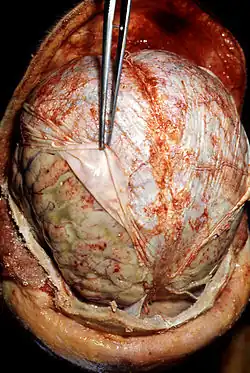

- Gross examination – the examination of diseased tissues with the naked eye. This is important especially for large tissue fragments, because the disease can often be visually identified. It is also at this step that the pathologist selects areas that will be processed for histopathology. The eye can sometimes be aided with a magnifying glass or a stereo microscope, especially when examining parasitic organisms.